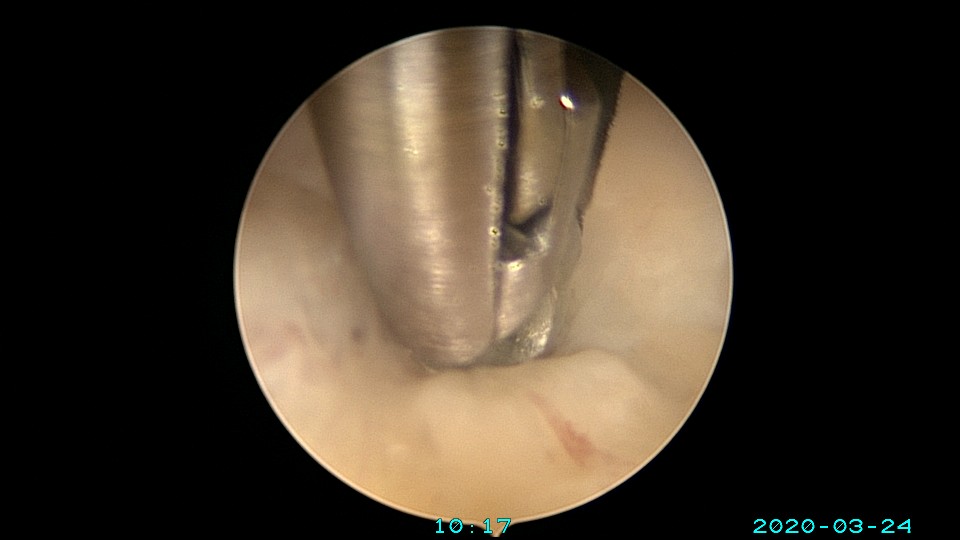

患者65岁,G1P1,顺产1次。安环30年,绝经10年。外阴白斑,阴道明显萎缩,无法置入扩阴器,阴道内镜方式找到宫颈外口,宫颈萎缩,穹隆几乎消失,无法夹持宫颈,宫颈管见多个息肉,宫颈内口狭窄坚硬,难以扩张。微型异物钳探查宫腔方向,用异物钳、微型剪刀扩大宫颈内口失败,改用双极电针切开宫颈内口,但镜子仍无法进入宫腔。用异物钳反复牵拉O型环至阴道内,中弯钳配合卵圆钳拉出节育环,环变形。有人问我何不用取环钩取环,这个病人探针和取环钩都无法发挥作用。